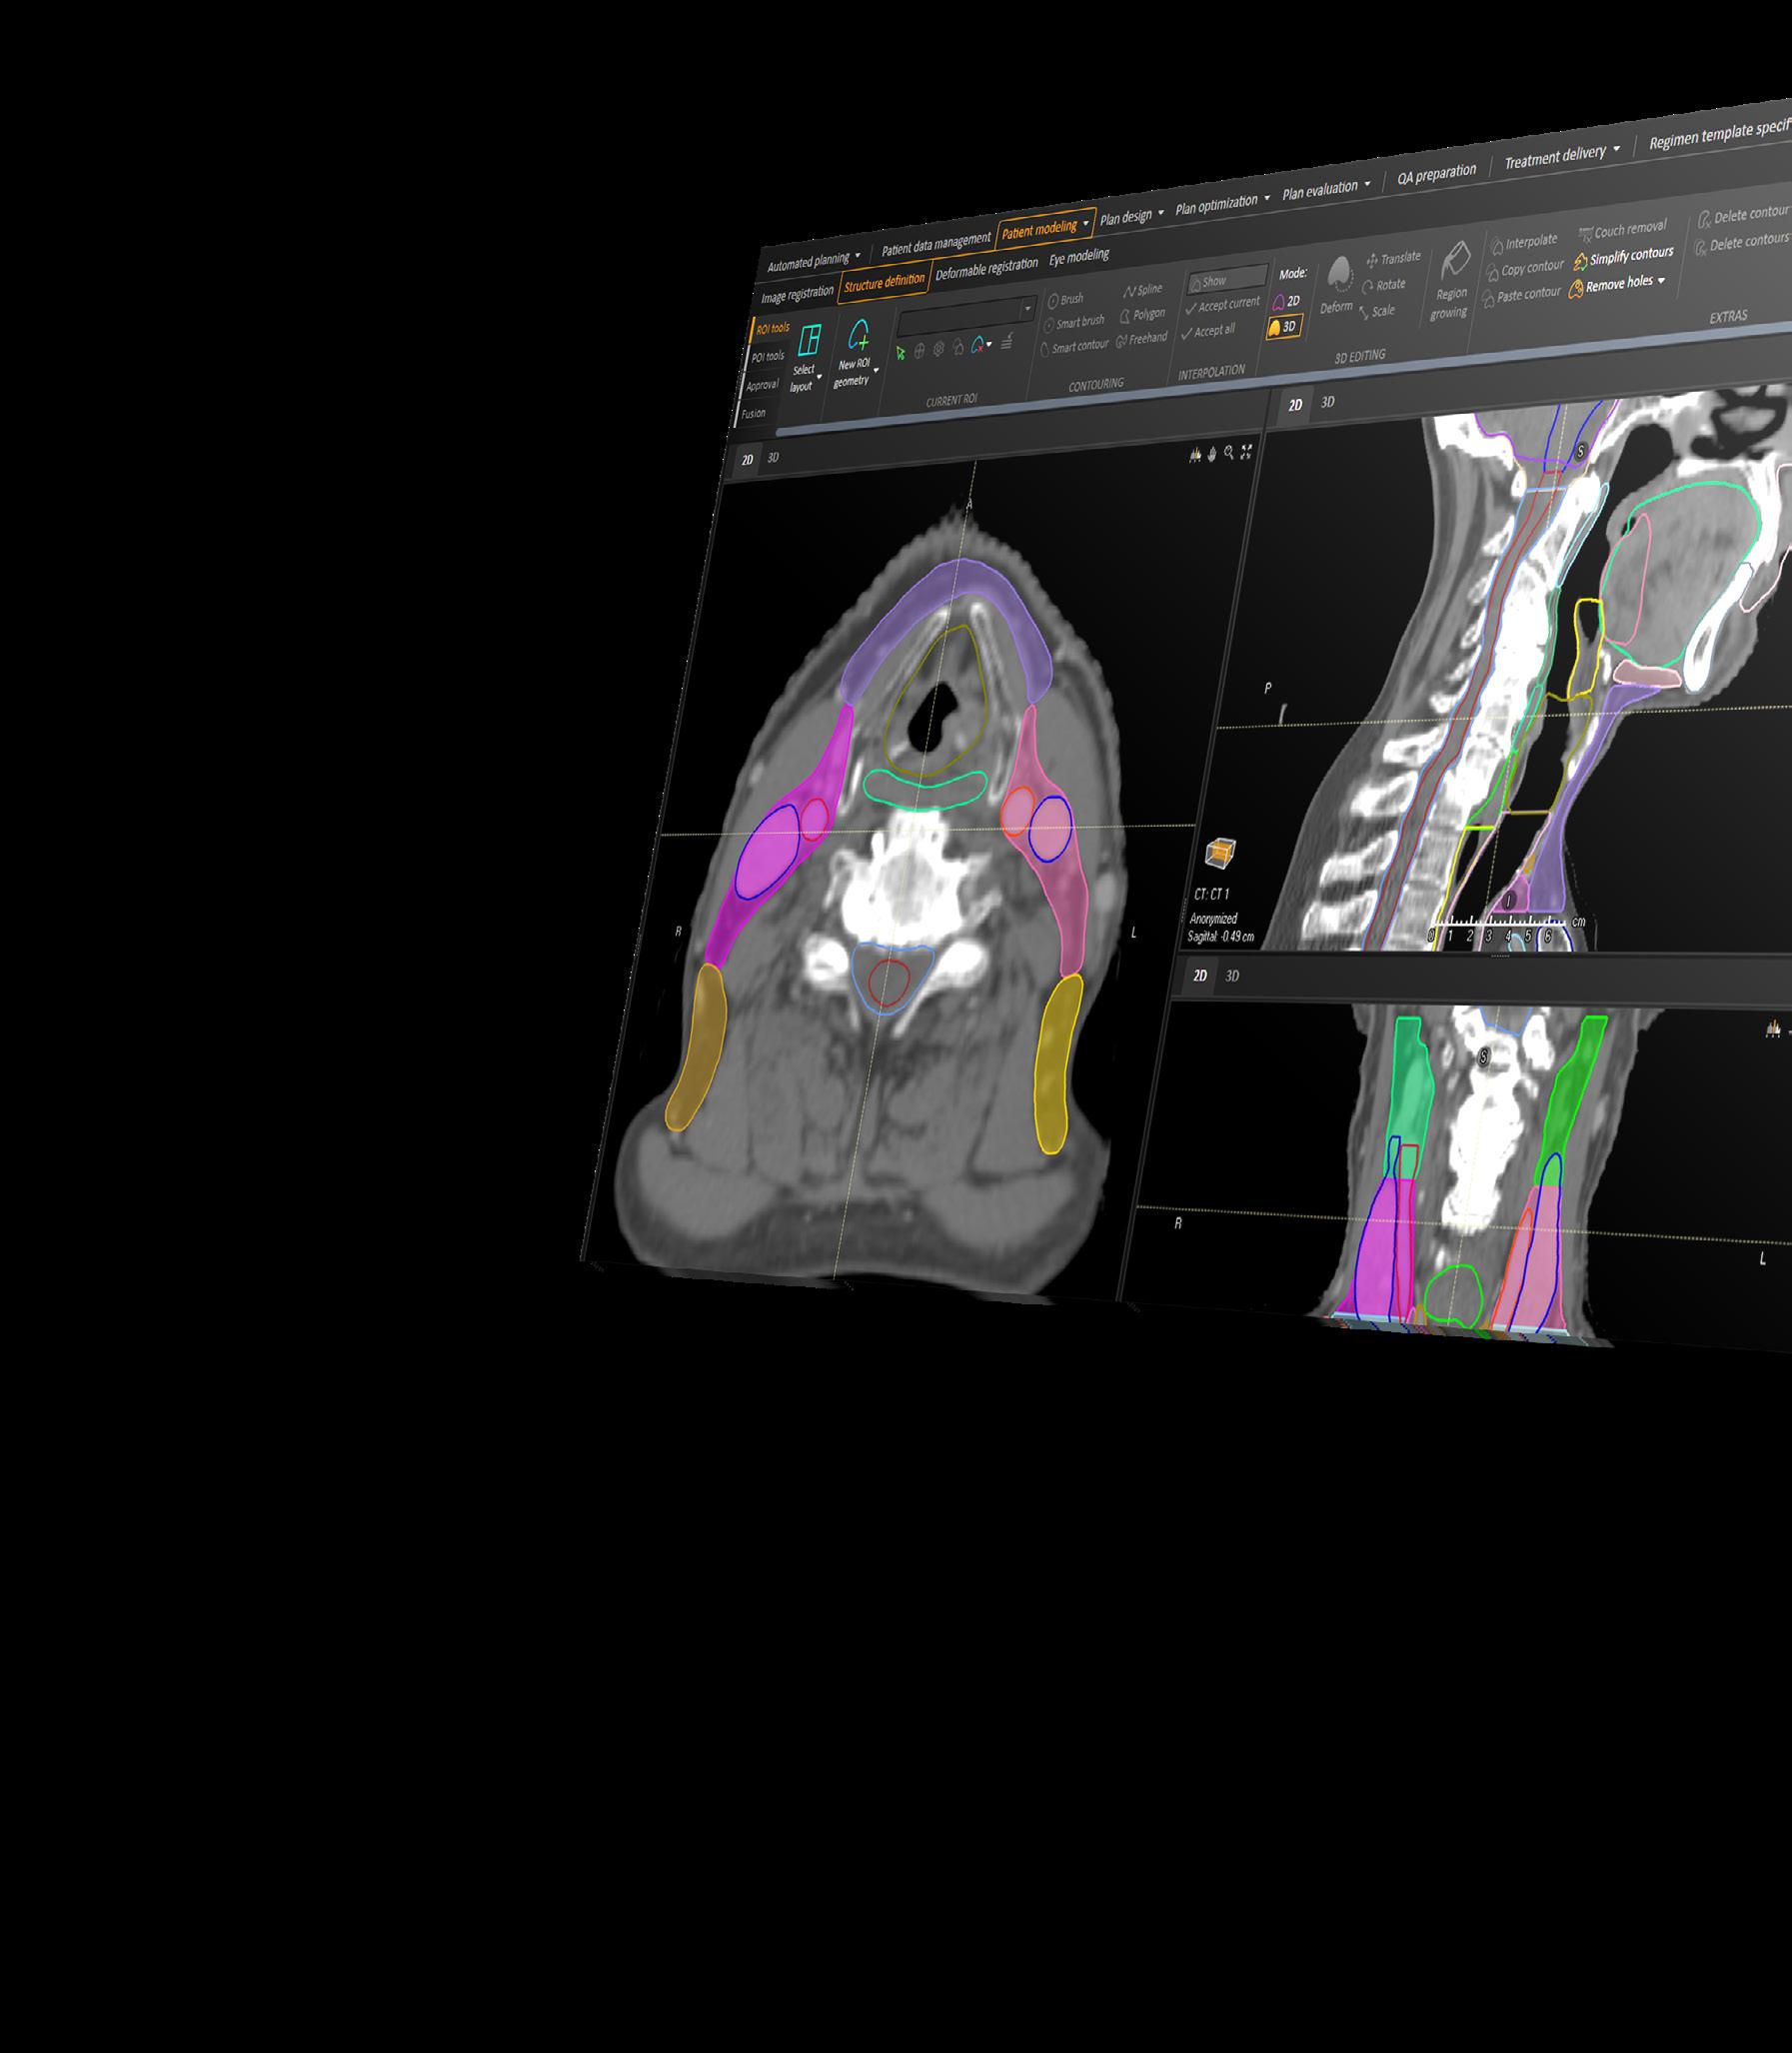

Deep learning capabilities in RayStation®* help make image segmentation quicker and more consistent. A high-speed GPUpowered algorithm is capable of producing consistent segmentation results using guideline-based segmentation models that have been trained and evaluated on curated data for different body sites.

HEAD AND NECK (OAR) CT

STRUCTURES

Bone_Mandible Larynx_SG IMPROVED

Brain Lens_L

Brainstem Lens_R

Cavity_Oral Lips

Cochlea_L Musc_Constrict_I

Cochlea_R Musc_Constrict_M

Cricopharyngeus

Eye_L

Musc_Constrict_S

Nasolacrimal_Duct_L

Eye_R Nasolacrimal_Duct_R

Fossa_Posterior OpticChiasm

Glnd_Lacrimal_L OpticNrv_L

Glnd_Lacrimal_R OpticNrv_R

Glnd_Submand_L Parotid_L

Glnd_Submand_R Parotid_R

Glottis IMPROVED Pituitary

Joint_TM_L SpinalCord

Joint_TM_R Tongue_Base

HEAD AND NECK (LYMPH NODE LEVELS) CT

LN_Neck_IA

LN_Neck _IB_L

LN_Neck _IB_R

LN_Neck _II_L

LN_Neck _II_R

LN_Neck _III_L

LN_Neck _III_R

LN_Neck _IVA_L

LN_Neck _VAB_L

LN_Neck _VAB_R

LN_Neck _VC_L

LN_Neck _VC_R

LN_Neck _VIA

LN_Neck _VIB

LN_Neck _VIIA_L

LN_Neck _VIIA_R

LN_Neck _IVA_R LN_Neck _VIIB_L

LN_Neck _IVB_L

LN_Neck _IVB_R

LN_Neck _VIIB_R